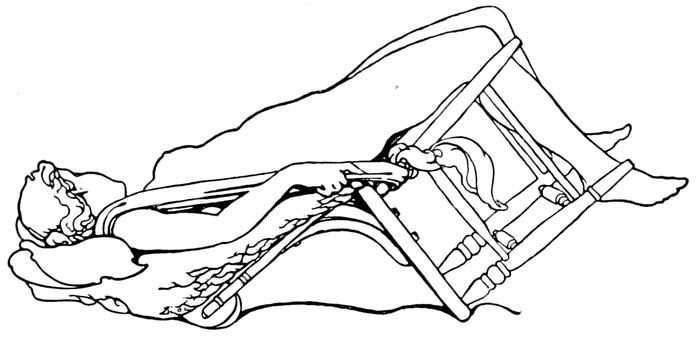

Delivery in side position |

141 |